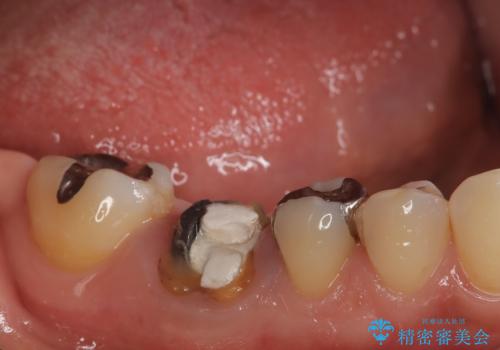

- 右下奥歯が虫歯で被せ物が取れてしまい、また噛めるようにしたいとのことで来院されました。

虫歯が大きく、歯を保存することが難しい状態でしたので、抜歯してインプラント治療を行うこととなりました。